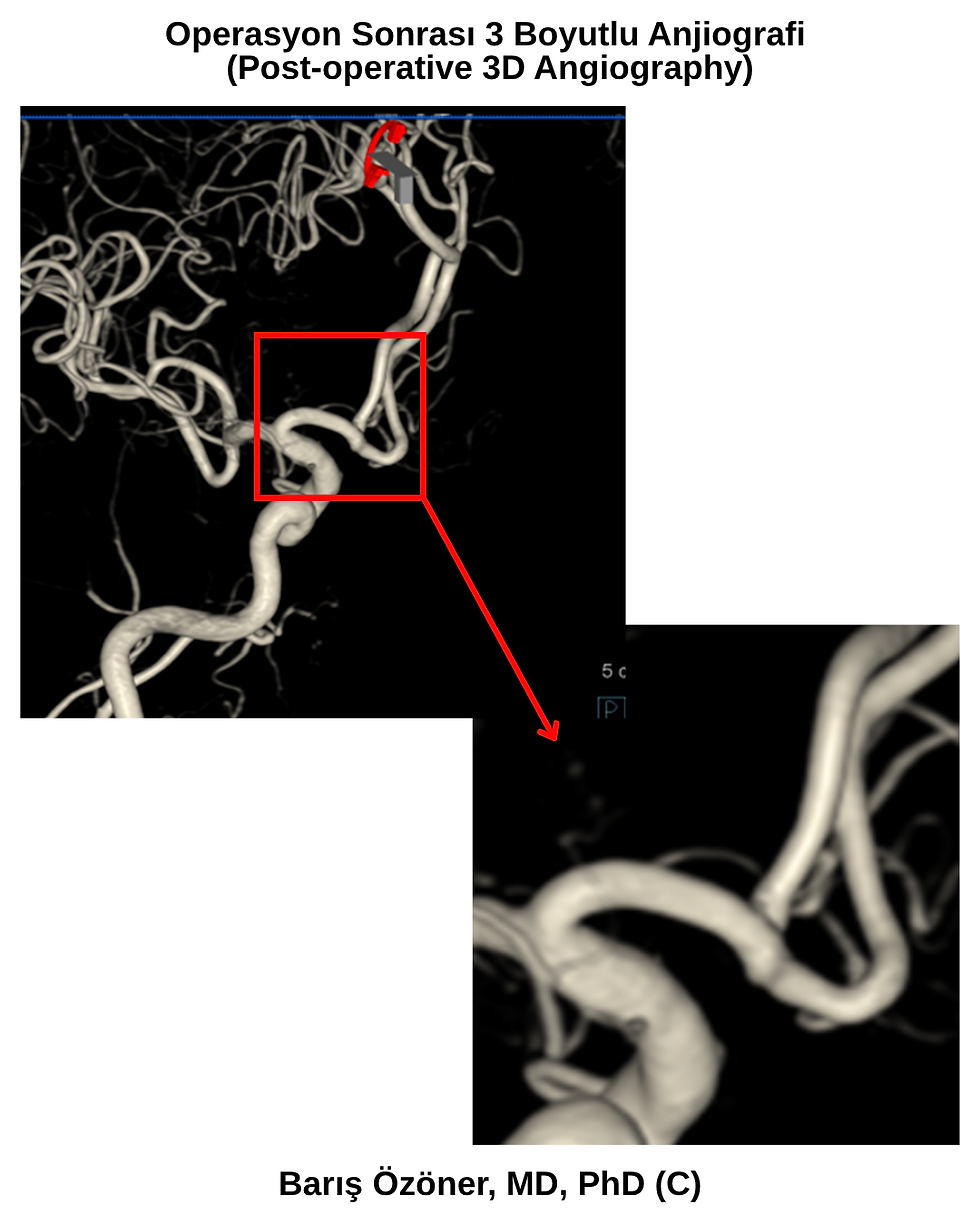

Paylaşılan ameliyat sonrası anjiyografi görüntülerinde:

Anevrizmanın tamamen kapatıldığı

Klipin doğru konumda olduğu

Ana damarların ve yan dalların açık kaldığı net bir şekilde görülmektedir.

Bu, başarılı bir cerrahi müdahalenin en önemli göstergesidir.